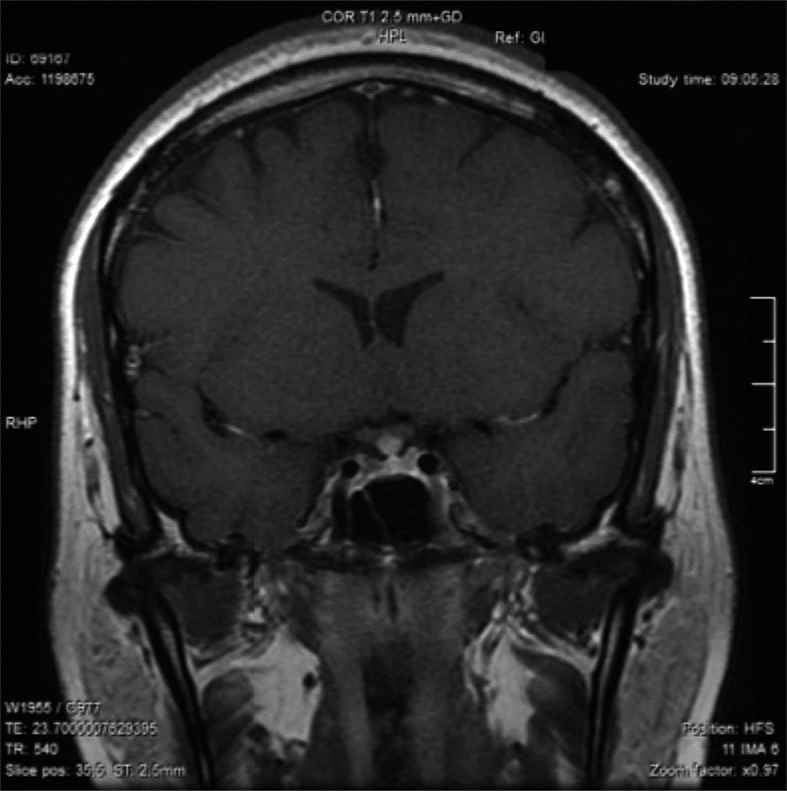

Posteriormente, consultó con especialista endocrinólogo donde se le solicitó exámenes que destacaba: glicemia 97 mg/dl, creatininemia 0,71 mg/dl, sodio 145 mEq/l, potasio 3,6 mEq/l, cloro 105 mEq/l, FSH 3,8 MUI/ml, Estradiol 12 pg/ml, prolactina 20,6 ng/ml, TSH 4,69 UI/ml, T4 libre 1,0 ng/dl, IGF-1 30,8 ng/ml (130-354), cortisol 151 ng/ml (40-230). Resonancia magnética (RM) de la región selar informó “silla turca normal, engrosamiento nodular del tercio medio distal del tallo hipofisiario y no se identifica señal de la neurohipófisis” (Figura 1). Se ajustó DDAVP a 2 puff en la mañana y 1 puff en la tarde, logrando ya normalizar la diuresis diurna y no tener nicturia. Se solicitó control RM en forma precoz para evaluar evolución de engrosamiento del tallo y segunda resonancia informó “no se identifica señal de neurohipófisis, evolución regresiva del engrosamiento del tallo hipofisiario respecto a RM previa” (Figura 2). Se establece diagnóstico de Infundibuloneurohipofisitis, Diabetes Insípida central y amenorrea secundaria por hipogonadismo hipogonadotrópico. La paciente evoluciona en forma adecuada, asintomática, con completo control de la diuresis, y dado el compromiso gonadal y la edad se inició terapia reemplazo hormonal. Siguiente RM evidenció normalización del grosor del tallo hipofisiario, sin evidenciar la neurohipófisis.

Figura 2. Evolución regresiva del engrosamiento del tallo hipofisiario.

Dentro del correcto diagnóstico de la INH está la neuroimagen, donde la RM es el método de elección. Los hallazgos comúnmente encontrados son el engrosamiento del infundíbulo y del tallo hipofisiario (se considera engrosamiento si es mayor a 4 mm) y la pérdida de señal de la neurohipófisis (hay que considerar que el 10% de la población normal no la presenta, especialmente en ancianos). Esta asociación, ausencia de señal de neurohipófisis y engrosamiento del tallo hipofisiario, son altamente sugerentes de INH. En nuestra paciente se encontraron ambos fenómenos, y considerando la regresión del engrosamiento del tallo hipofisiario lo hacía compatible con INH. La adenohipófisis en la RM es usualmente normal en tamaño e intesidad a la señal. Siendo el engrosamiento del tallo hipofisiario el hallazgo cardinal a la imagenología, inicialmente se le denominaba “Stalkitis” a esta entidad10; sin embargo, la denominación INH es la más idónea debido a que anatomopatológicamente el compromiso es del infundíbulo, tallo y neurohipófisis. Respecto al engrosamiento del tallo hipofisiario en muy importante considerar su diagnóstico diferencial9. Una adecuada historia clínica, manifestaciones clínicas, imagenología y en ocasiones biopsia darán el diagnóstico adecuado. En la Tabla 1 se enumeran las etiologías de engrosamientos del tallo hipofisiario aisladas.